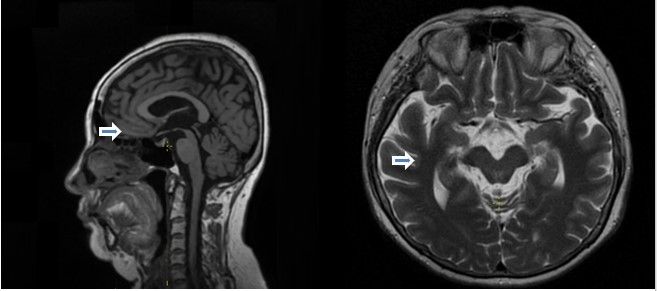

Результаты МРТ головного мозга от ноября 2024 года (Рис. 1): «МР-признаки нейродегенеративного процесса с преимущественным поражением среднего мозга (средний мозг уменьшен в объёме, соотношение «средний мозг-мост» уменьшено до 0,18 (референс от 0,24), симптомы «колибри» и «Микки-Мауса» (возможный прогрессирующий надъядерный паралич). Очаговые изменения белого вещества мозга сосудистого характера категории Fazekas 1. Глобальная корковая атрофия (GCA) 1 степени. Признаки внутричерепной гипертензии, либо исхода внутричерепной гипертензии (коррелировать с клиническими проявлениями)». УЗИ БЦА от ноября 2024 года: «Признаки начального атеросклероза БЦА в виде увеличения толщины комплекса интима-медиа (ТИМ) в каротидной бифуркации справа. Волнообразная деформация правой внутренней сонной артерии (ВСА) и С-образная деформация правой позвоночной артерии (ПА) в VI сегменте без локальных нарушений кровотока. Гипоплазия правой левой ПА. Снижение скоростных показателей кровотока по левой ПА в V1-2 сегментах».

Рис. 1. Регистрация симптома «колибри» и «Мики-Мауса» (указано стрелкой) на МРТ-изображении головного мозга в сагиттальных и аксиальных проекциях, больная Ж., 61 год.

Fig. 1. Registration of «hummingbird» and «Mickey Mouse» signs on the MRI image in sagittal and axial projections, patient G., 61 years old.

Наиболее ярким и существенным феноменом является диссоциация клинических проявлений с данными нейровизуализации. Две пациентки, примерно одного возраста, с приблизительно одной длительностью заболевания и степенью выраженности клинической картины демонстрируют разную степень поражения и вовлеченности структур головного мозга по данным МРТ диагностики: если в первом случае у пациентки с классической картиной ПНП обнаружены симптомы «Микки-Мауса» и «колибри», то во втором случае на фоне выраженной картины поражения головного мозга, МРТ изображения не демонстрируют характерных признаков.

Представленная клиническая картина надъядерного пареза вертикального взора (особенно, при взгляде вниз), ранних постуральных нарушений с падениями назад, псевдобульбарного синдрома, аксиальной ригидности в сочетании с характерными изменениями на МРТ (симптом "колибри", "Мики-Мауса") с высокой долей вероятности указывает на прогрессирующий надъядерный паралич (синдром Ричардсона) по критериям шкалы MDS (2017) для пациентки Ж.: О1+Р1, дополнительные критерии - А2, С2, СС2, IF1, для пациентки М.: О1+Р2, дополнительные критерии А2, С1-2, СС2. Недостаточная или отсутствующая эффективность ответа на терапию леводопой и неуклонное прогрессирование симптоматики подтверждает нейродегенеративную природу заболевания. Дальнейшая тактика должна быть направлена на симптоматическое лечение, реабилитацию и поддержку пациента и его семьи.